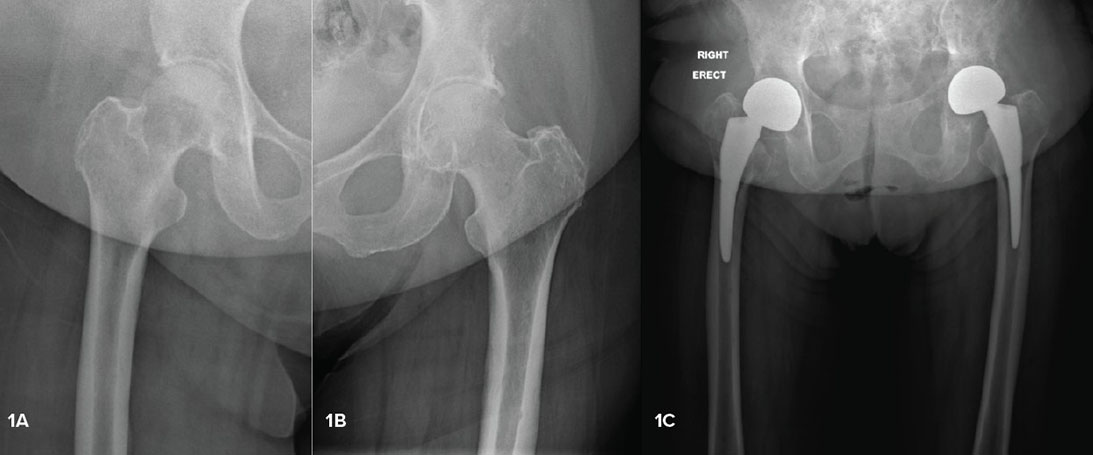

Hip replacement in metastatic disease: Guidance for the non-oncology surgeon

Orthopaedic surgeons will increasingly be needed to care for oncology patients with pathologic fractures, infection, and other complications.